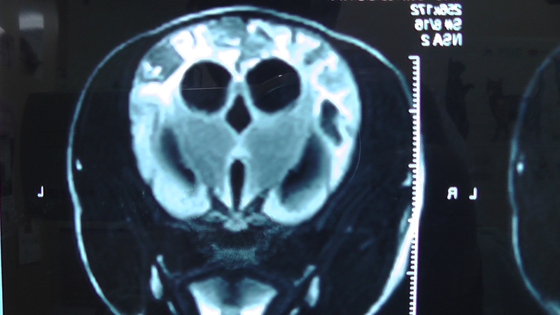

下の画像はMRIで撮影された脳炎の画像です。この症例は犬で3~4歳から痙攣が始まり、以降 3年間、抗痙攣薬を投薬していましたが、それでも痙攣の頻度が高くなったため来院されたました。当院で、身体検査と神経学的検査を実施し、紹介した大学病院でMRI撮影と脳脊髄検査を実施して脳炎が判明しました。